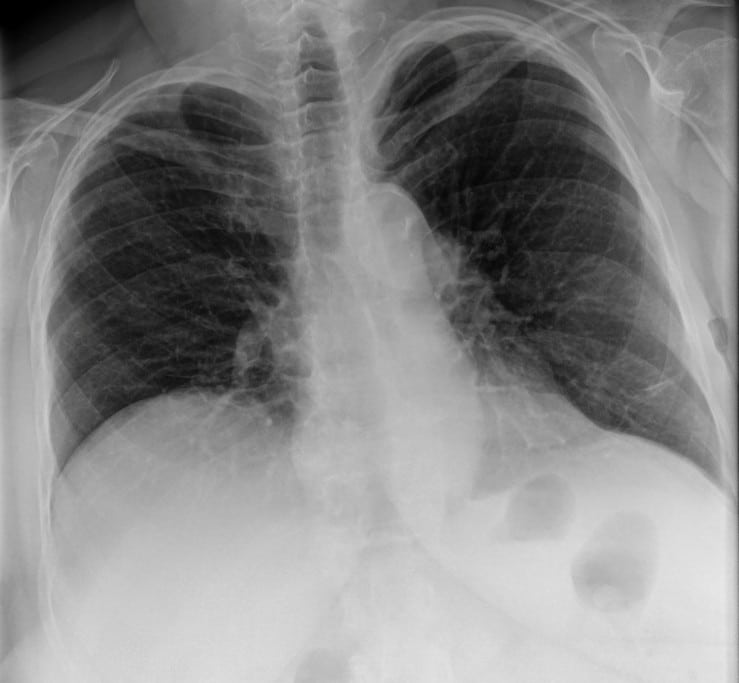

This 67-year old female patient presented to the ER with shortness of breath, in conjunction with chronic pain in her posterior thoracic region upon taking a large breath in. The reading radiologist noticed a suspicious mass-like opacity in the Lateral view. The radiologist stated that, thanks to the DE images, they could they tell the opacity wasn’t a lung mass, but instead far less concerning bony outcroppings from the thoracic vertebrae.